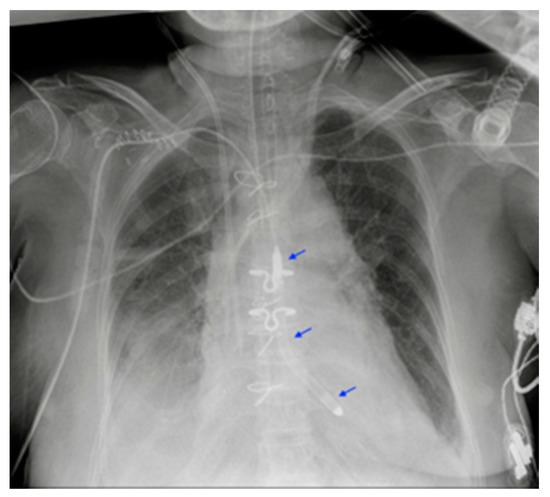

5.3. Ventricular Assistance Devices (VADs)

5.4. Impella